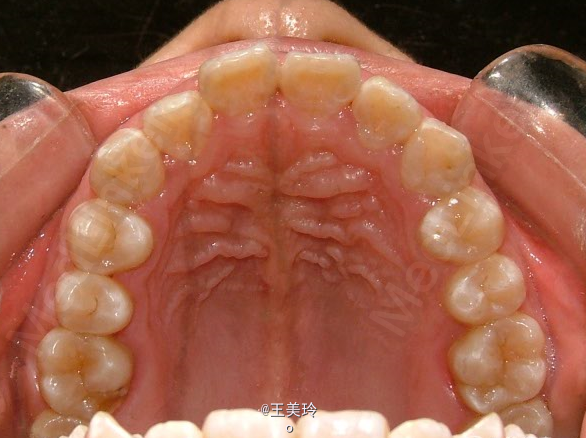

主诉:面突求矫治 既往史:无矫治史,无牙科治疗史,无外伤史,无过敏史,无口腔不良习惯,无家族遗传史 口腔检查:恒牙列,A7-B7;C7-D7。个别牙齿不齐 尖牙磨牙I类关系轻度深覆合深覆盖 下颌中线右偏约2mm 双颌前突,突面型 关节无弹响无压痛

诊断:安氏I类双颌前突 矫治计划 1.MBT矫治技术 2.拔牙矫治,拔A4B4C4D4 3.闭隙曲,J勾内收前牙 4.矫治结束后尖牙,磨牙,覆合覆盖正常 5.面型有所改善